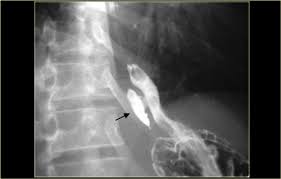

Definition cmv esophagitis is an infection of the esophagus caused by the cytomegalovirus (cmv). The endoscopic findings in hsv esophagitis vary with the interval between esophageal infection and endoscopic examination. If left untreated, esophagitis can damage the lining of the. Clinical effect of itopride hydrochloride on the digestive symptoms of chronic gastritis with reflux esophagitis // clin. A clinical case in a child was given. The aims of this study were to investigate the implications of the endoscopic findings for the. Cytomegalovirus esophagitis is a form of esophagitis associated with cytomegalovirus. Causes of esophagitis include stomach acids backing up into the esophagus treatment for esophagitis depends on the underlying cause and the severity of tissue damage. Comorbid occurrence of laryngeal or pulmonary disease with esophagitis in united states military veterans // gastroenterology. Videoradiography with lateral/ap views are the optimal studies. Esophagitis can cause painful, difficult swallowing and chest pain. As the practice shows, hypodiagnostics of eosinophilic esophagitis and other eosinophilic gastrointestinal diseases takes place. Eosinophilic esophagitis attributed to gastroesophageal re.

Cytomegalovirus esophagitis is a form of esophagitis associated with cytomegalovirus. As the practice shows, hypodiagnostics of eosinophilic esophagitis and other eosinophilic gastrointestinal diseases takes place. Evaluation and management of infectious esophagitis in immunocompromised and immunocompetent individuals. Videoradiography with lateral/ap views are the optimal studies. Cobblestone esophagitis (эзофагит со слизистой булыжной мостовой).

Epidemiology and infectious complications of human immunodeficiency virus antibody positive patients. In contrast, cmv esophagitis often occurs as part of a disseminated cmv infection that can involve the stomach, intestine, and a number of other organs. Cytomegalovirus esophagitis is a form of esophagitis associated with cytomegalovirus. This condition occurs in the setting of patients with a weakened immune system who are susceptible. Esophagitis can cause painful, difficult swallowing and chest pain. The endoscopic findings in hsv esophagitis vary with the interval between esophageal infection and endoscopic examination. Associated with cmv or hsv esophagitis in immunocompromised (see case reports below); I may be used for up to 8 weeks to treat all grades of erosive esophagitis.